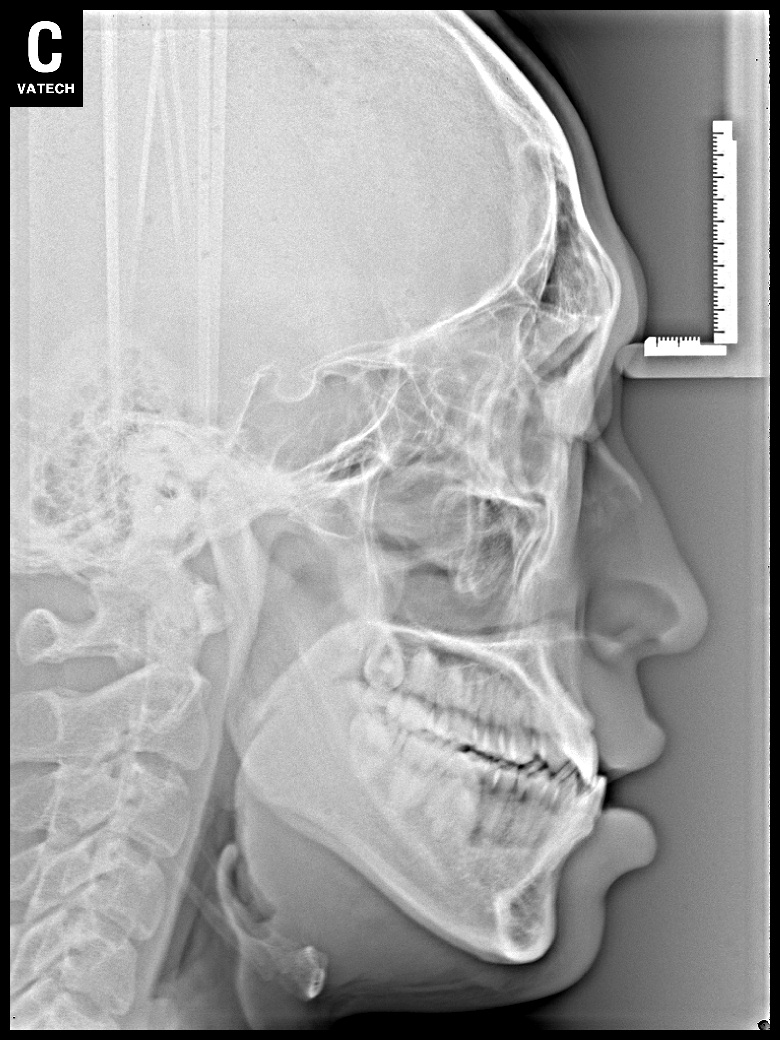

치료 후 사진입니다.